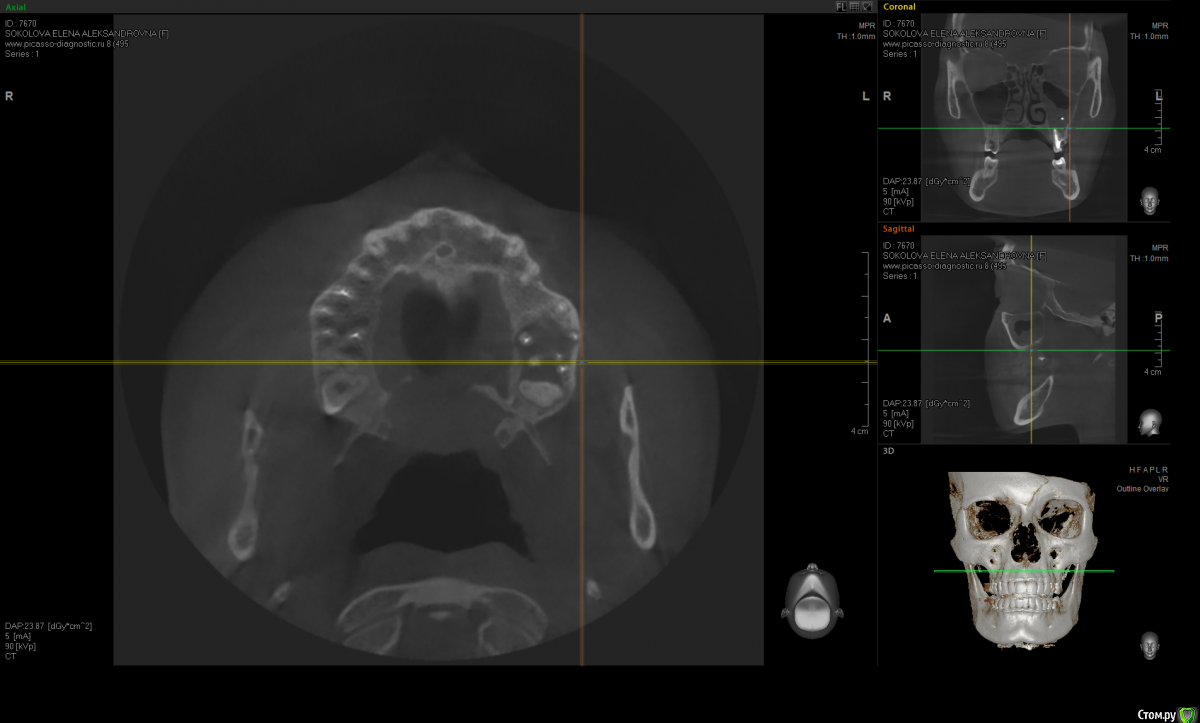

Kostoprav Опубликовано 20 июня, 2015 Поделиться Опубликовано 20 июня, 2015 по данным кт сканам определяеться одонтогенная радикулярная киста в\ч в обл 6,7,8 зубов проросшая в гайморову пазуху + инородное тело (пломбировочный материал ) По моему это работа наша , а не лориков , только санация пазухи не решит проблему Ссылка на комментарий